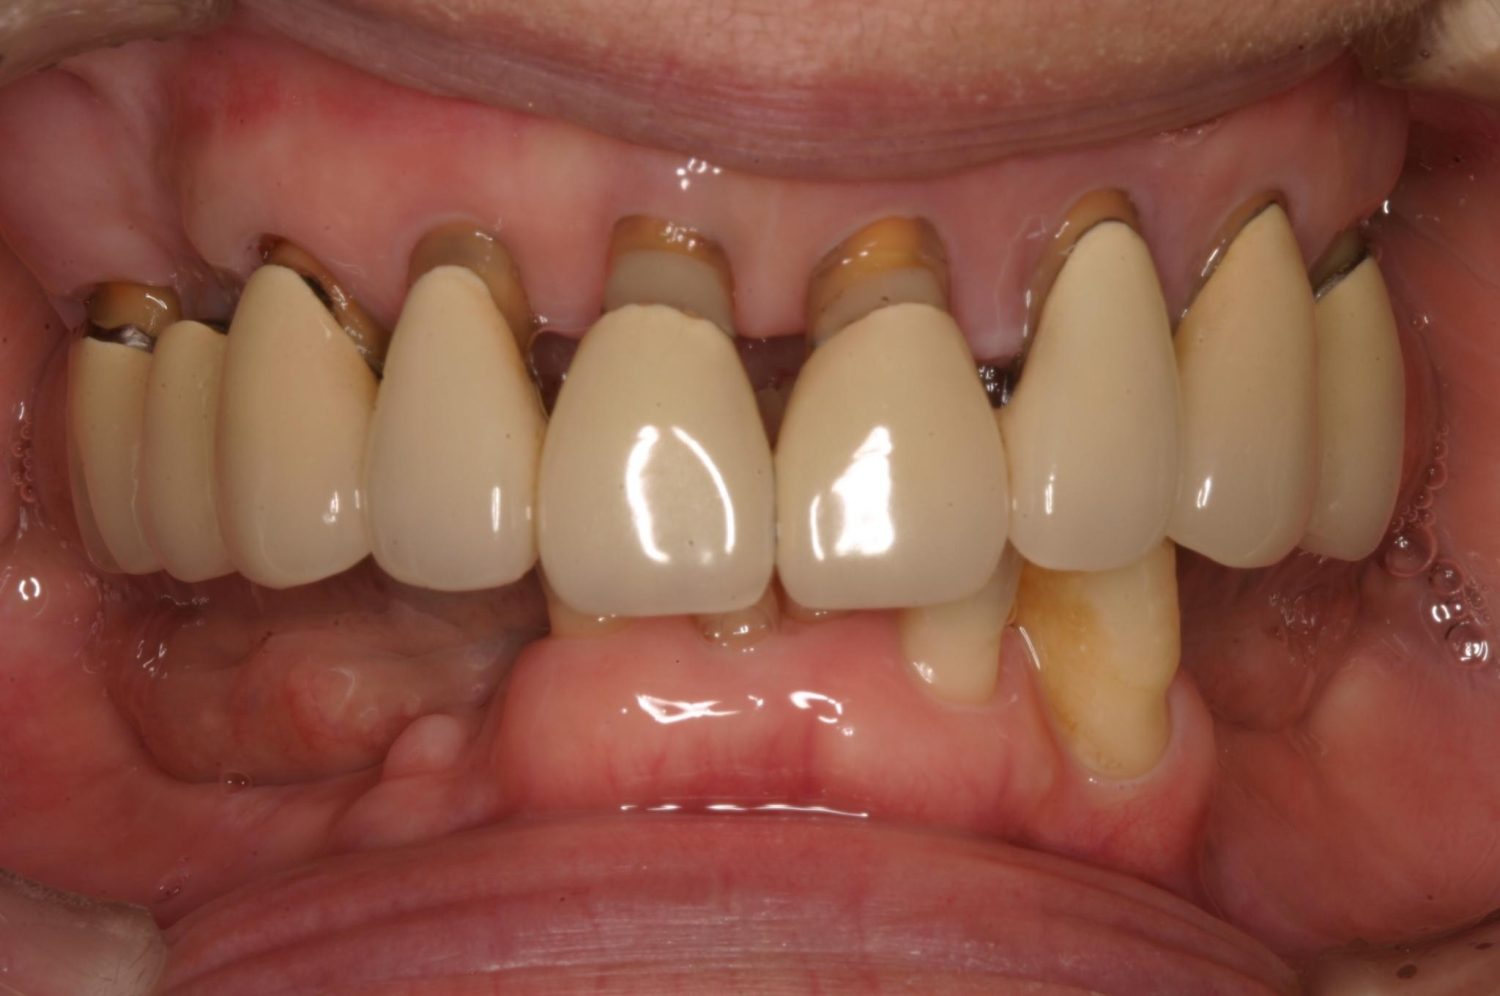

インプラント治療の症例紹介③

Before

After

主訴

むし歯の治療

治療内容

保存不可能な歯の抜歯

下顎にインプラント埋入し咬合再構成

治療費

2,688,400円(税込)

治療期間

14か月

治療回数

21回

想定されたリスク

※上部構造の形態が複雑になるため清掃が難しくなる。インプラント周囲炎の恐れがありました。

多数歯う蝕および多数歯欠損による咬合崩壊、保存不可能な歯の抜歯により上下無歯顎に。下顎に6本インプラント埋入する事で咬合再構成を行った。